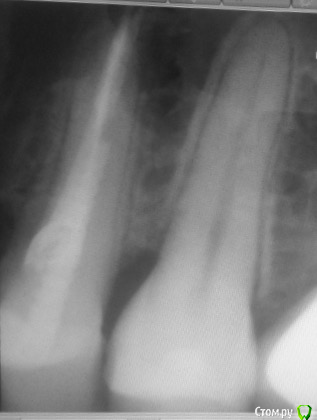

Никто не знает что с этим делать, сказали что пища попадает из за этого подтекает, Ещё 8 на имплант давит и может его расшатать правда такое возможно? Сказали купить ирригатор и постоянно мазать метрогилом. Нерв удалён почти 10 лет назад, пролечен зуб качественно, карман и свищ образовались в этом году.

Вот старый снимок, лучше видно как залечен зуб и свежее фото, сохраняется отёк, болит если надавливать.